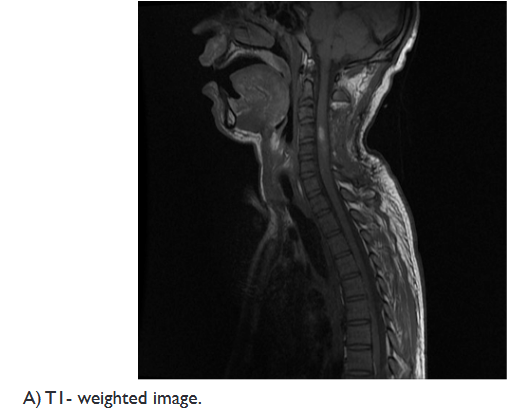

On examination, the muscle strength of the upper extremity was 2/5, and 3/5 in his lower extremity, with a positive Hoffman’s and Babinski’s signs. A spinal MRI revealed an intramedullary cystic mass, at level of C4, with ring enhancement after injection of gadolinium, associated with perilesional edema extending from the level of C2 to C7 (Figure 1).

Figure 1 Preoperative sagittal MRI of the cervical spinal cord.

Spinal MRI is the exam of choice; it provides good demonstrations of the size of the lesion, its location, and identifies any associated spinal cord abnormalities.17

Murphy et al. reported that the presentations of ISCA on MRI are similar to those of a cerebral abscess. In the early stages of infectious myelitis, MRI shows high-signal intensities on T2WI. The lesion reveals poorly defined enhancement on T1WI with contrast. One week later, the lesion becomes less diffusely hyper-intense on T2WI. The marginal enhancement is clearly defined on T1WI with contrast. Diffuse marginal cord edema was also noted.18